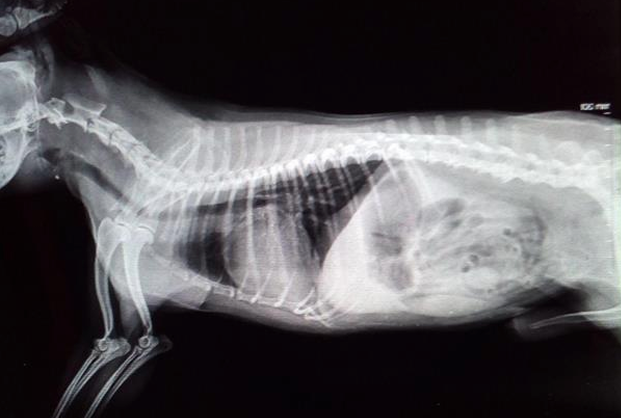

- bronchopneumonia with pre-existing pleural effusion

- the lung has no well-defined margin